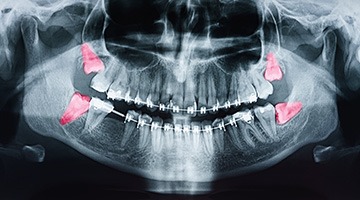

The wisdom tooth extraction procedure is surprisingly straightforward. After you’ve met with Dr. Branberg for your consultation, he’ll be able to determine if your wisdom teeth need to come out after inspecting your smile, taking X-rays, and discussing your symptoms with you. From there, a treatment plan is put together.

Partially erupted wisdom teeth can normally be loosened and then gently removed using specialized instruments; however, in the case of fully impacted wisdom teeth, a small oral surgery may be necessary. During this approach, the teeth are normally removed in sections to minimize the amount of bone loss and tissue disruption. In any case, our team will closely monitor you throughout the process and do everything we can to ensure your comfort and speedy recovery!